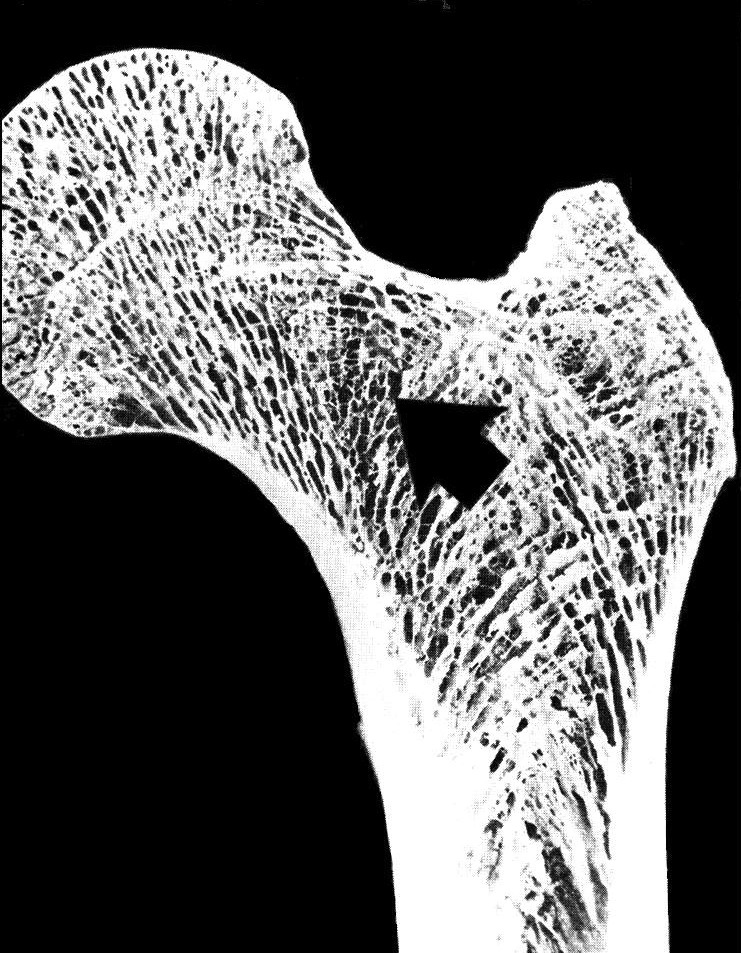

Identify the portion that is spongy bone

Identify the portion that is compact bone